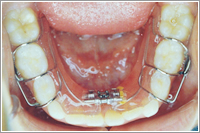

8歳ごろまでは側方拡大装置を使用し顎を広げることででこぼこの緩和ができます。